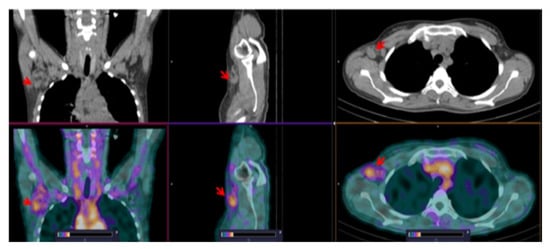

3.3. [99mTc]Tc-TG SPECT/CT Imaging of Nodal and Extranodal Lesions